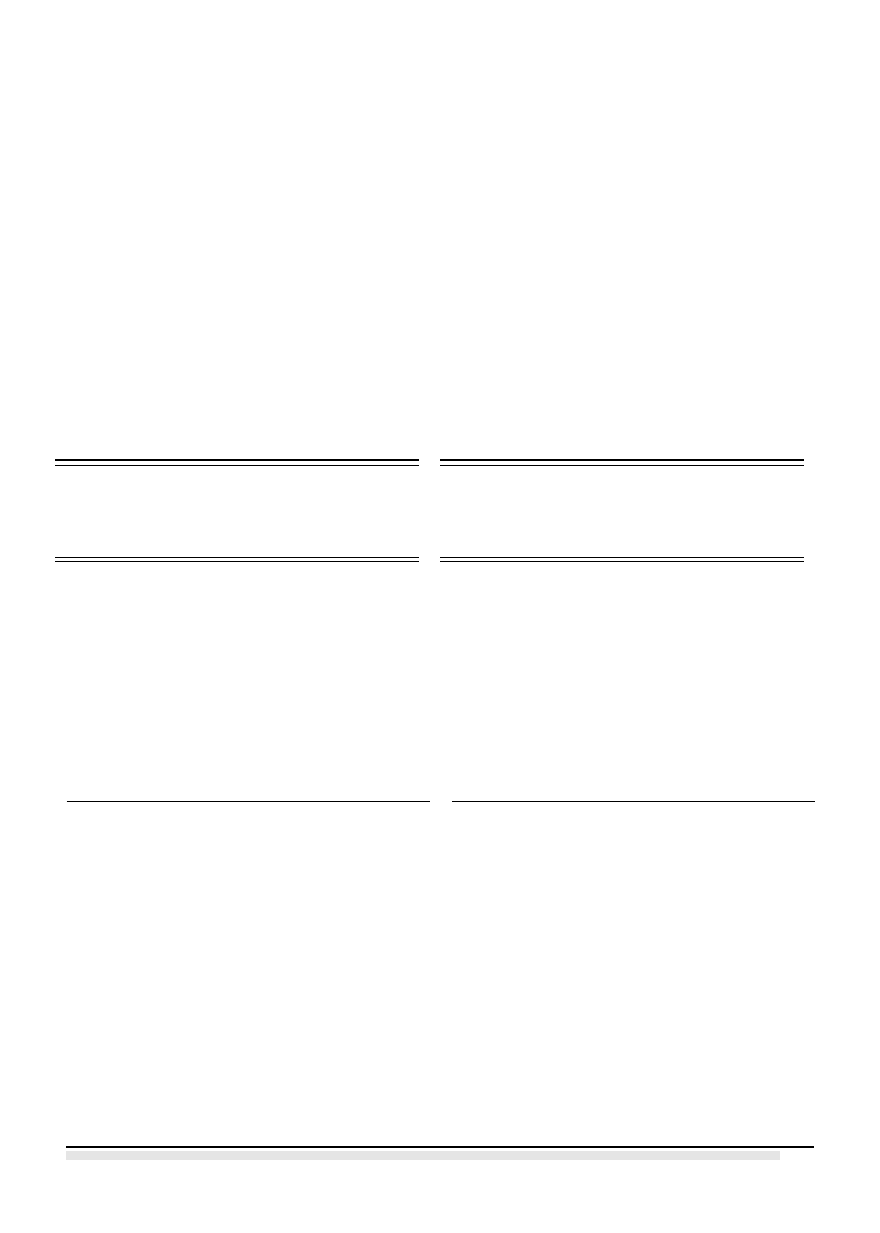

Do gabinetu zgłosiła się pacjentka M. Sz.-P. lat

60 celem wymiany dotychczas użytkowanych mo-

stów metalowo-ceramicznych w zakresie 12-16 i

24-25 oraz poprawy estetyki zębów przednich za-

równo w szczęce jak i w żuchwie. (ryc. 1)

Badaniem klinicznym stwierdzono most meta-

lowo-ceramiczny 16-12 (zęby filarowe: 16, 13, 12,

przęsło 15, 14), zęby 11, 21, 22, 23, most jedno-

brzeżny na filarze 25 z dowieszonym przęsłem

Ryc. 1. Stan przed wykonaniem uzupełnienia.